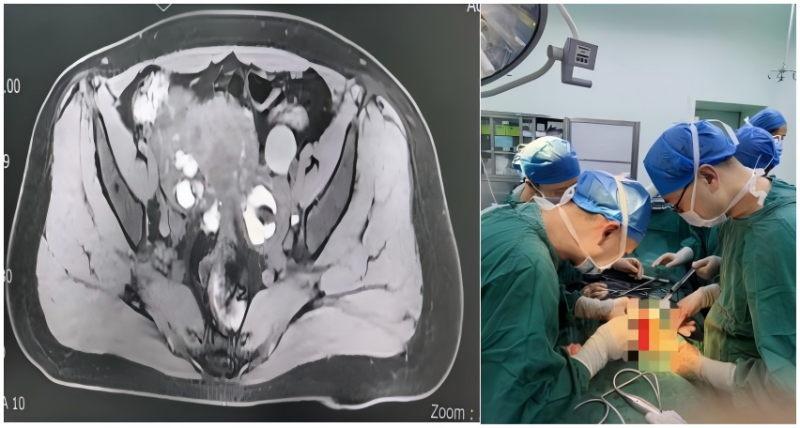

依托医院多学科协作平台,在党支部及医务科的统筹指导下,妇产科、泌尿科、放射科、重症医学科、麻醉科等多科室党员和技术骨干积极参与,开展多次术前联合讨论。术前CT显示患者子宫增大、双侧卵巢囊肿、盆腹腔重度粘连,同时伴有一侧肾脏明显长大、肾盂重度扩张。手术迫在眉睫,团队围绕“彻底切除病灶、最大限度保护生育功能、精确修复输尿管、解除肾积水”的整体目标,精心准备手术方案,并制定多套应急预案,全力保障手术安全。

手术期间中,党员专家们以精湛技艺紧密配合:妇产科马超主任团队耐心细致分离盆腔粘连,完整的切除了异位病灶,为后续操作扫清障碍;泌尿外科刘强主任团队精准定位受损输尿管,实施精细修复重建。整个手术过程中,党员同志冲锋在前、严谨细致,凭借扎实的专业功底和无畏的担当精神,顺利完成了这场高难度手术。术后复查CT显示,患者肾脏形态基本恢复正常,原重度扩张的肾盂已完全回缩,经团队精心照护,患者术后一周顺利康复出院。